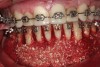

Fig 11. Interim orthodontic phase and transitional bonding to be accomplished based on Bolton analysis now that overly sufficient space has been appropriated for the creation of proportionately correct mandibular incisors. Once transitional bonding is complete, orthodontic finishing will be performed and any remaining spaces closed.

Figure 11